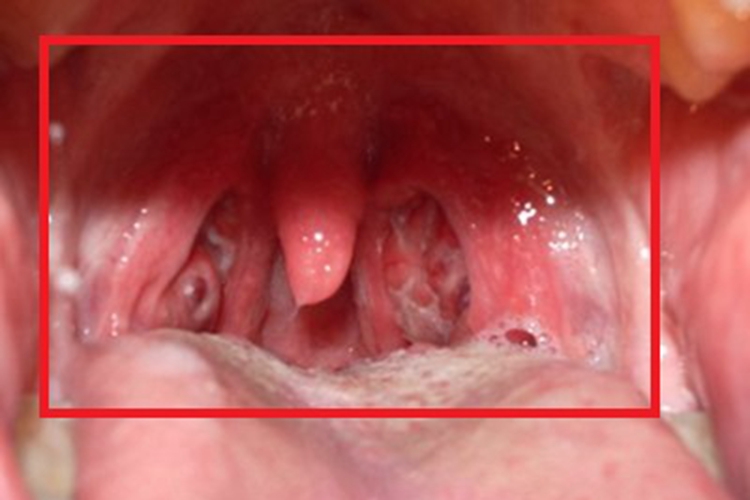

慢性咽炎可导致咽喉黏膜出现不同程度的充血、红肿,同时血管扩张,咽后壁有散在淋巴滤泡增生,可为散在分布,也可融合呈包块,常有少量黏稠分泌物附着在黏膜表面,患者可出现咽部异物感、痒感、干燥感等不适。

若存在淋巴滤泡增生,可用激光、低温等离子治疗,亦可进行冷冻、电凝固法等治疗。